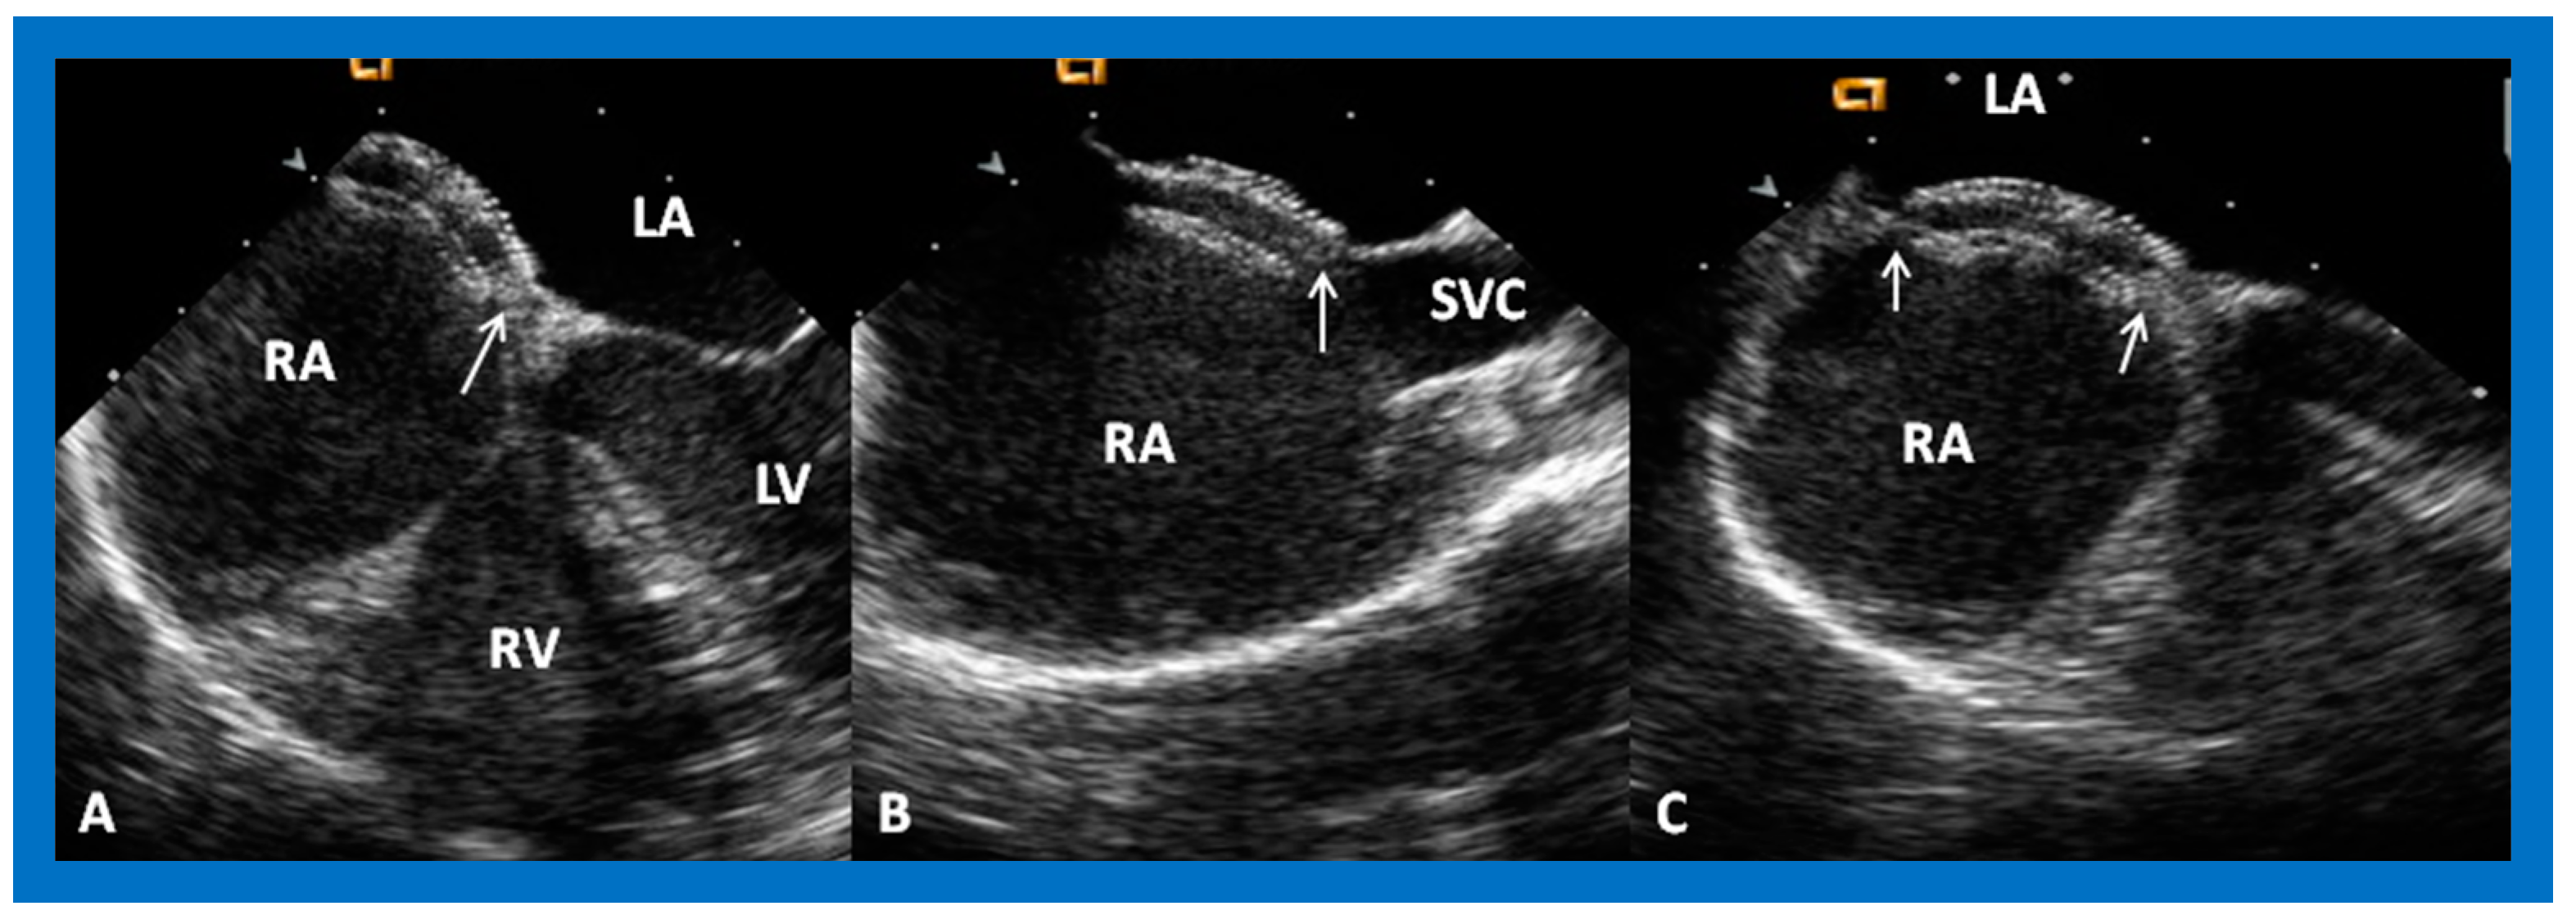

8.5. Septal Rims

9. Follow-Up after Device Occlusion

9.2. Device Position